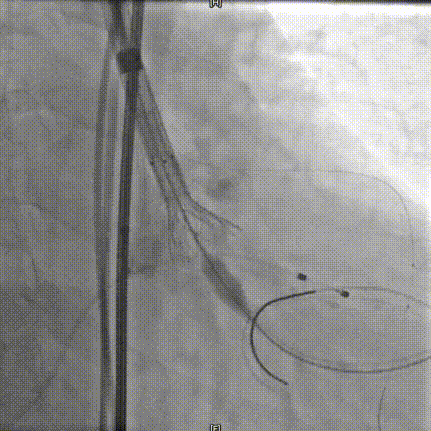

AV26瓣膜释放到工作位

AV26瓣膜工作位造影检查

AV26瓣膜释放

完全释放后造影

术中20mm球囊预扩可见轻微腰征,轻微瓣周漏,左冠充盈速度减慢,为保证患者安全,决定行冠脉保护,预防冠脉阻挡风险。选择AV26瓣膜,TaurusElite AV26瓣膜送至主动脉弓,输送系统轻松过弓及跨瓣,精准定位无冠窦最低点。

TaurusElite AV26瓣膜第一次释放定位位置接近瓣环,李怡教授准确定位判断,零位释放,瓣膜在手术计划的位置牢牢站稳了!手术过程行云流水,团队配合默契,操作细致熟练,主动脉根部造影及食道超声均只有少量瓣周漏;压差由术前的100mmHg直线下降到术后的5mmHg以内,TaurusElite首秀成功!